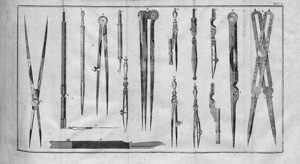

Ebermaier, Johann Erdwin Christoph

Taschenbuch der Chirurgie

Nachverkaufspreis

100€ (US$ 114)